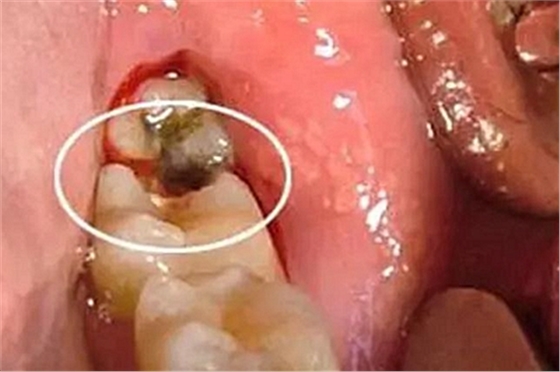

2、局部促進因素的檢查

檢查有無不良的義齒或固定冠、橋,有無鄰面充填體的懸突,或不良的正畸矯治器,修復(fù)材料的表面是否光潔,有無錯殆、不良習(xí)慣、食物嵌塞、解剖異常等(如畸形舌側(cè)溝、附著齦過窄、系帶附著異常等)。